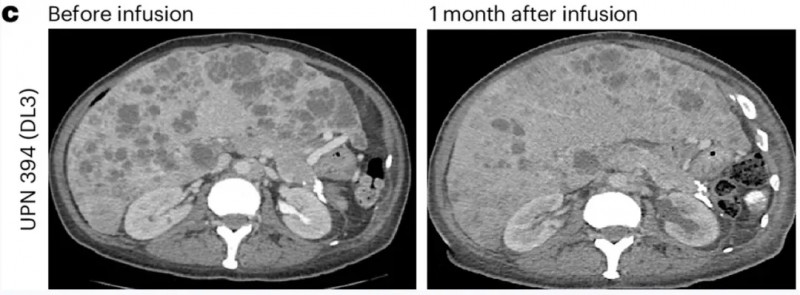

近期,世界知名期刊《Nature Medicine》报道了一项新型PSCA-CAR-T细胞疗法的首次人体1期临床试验(NCT03873805)。该试验共入组14例患者,均为PSCA阳性的转移性去势抵抗性前列腺癌(mCRPC)——癌细胞已扩散至前列腺外,且对激素治疗耐药,临床已无更优治疗方案,最终接受CAR-T细胞回输治疗。

结果显示:DL1、DL2、DL3三个剂量组患者的6个月生存率分别为33%、67%、40%。

值得关注的是,两例患者的治疗效果尤为亮眼,具体疗效如下:

另一例为前列腺癌伴胰腺转移患者(UPN388):输注PSCA-CAR-T前后的CT复查显示,输注前病灶大小为40.2×24.8mm,输注后1个月病变完全消退、已无法测量(详见下图e);尽管因存在骨转移,RECIST评估结果为“病情稳定”,但患者软组织转移灶的放射学表现已有所改善(详见下图b)。

▲图源“Nature Medicine”,版权归原作者所有,如无意中侵犯了知识产权,请联系我们删除